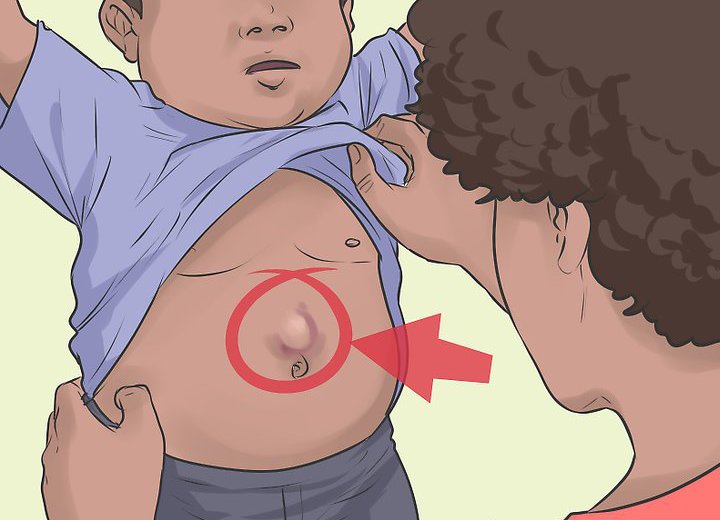

У ребенка торчит пупок чаще всего при наличии грыжи, реже у новорожденных наблюдается свищ.

Пупочную грыжу можно распознать по следующим признакам:

- Выпячивание увеличивается, если малыш тужится. Его сильнее видно, когда ребенок стоит;

- В грыжевом мешочке может находиться часть кишечника, тогда во время ощупывания можно ощутить урчание. При большом размере грыжи заметно шевеление кишечных петель;

Грыжа

Точно диагностировать патологию может только хирург после осмотра.

Самое частое объяснение того, что у ребенка может выпятиться пупок, – это грыжа. Обычно она носит врожденный характер и становится заметной на втором месяце жизни крохи. В норме после обрезания пуповины пупочное кольцо стягивается, сжимается. Если этого не происходит, или оно не закрывается до конца, формируется выпячивание. Особенно оно заметно, когда ребенок плачет или кашляет. Любое напряжение мышц живота выдает грыжу. Причем в обычном состоянии, когда малыш лежит, он спокоен, она может и не выдавать себя.

Образование грыжи связывают с незрелостью мышц, задержкой развития ребенка в утробе. Обычно ее можно убрать нажатием, но вправлять самостоятельно не рекомендуют. Любые отклонения должны наблюдаться врачом, действовать необходимо, опираясь на его назначения и советы.